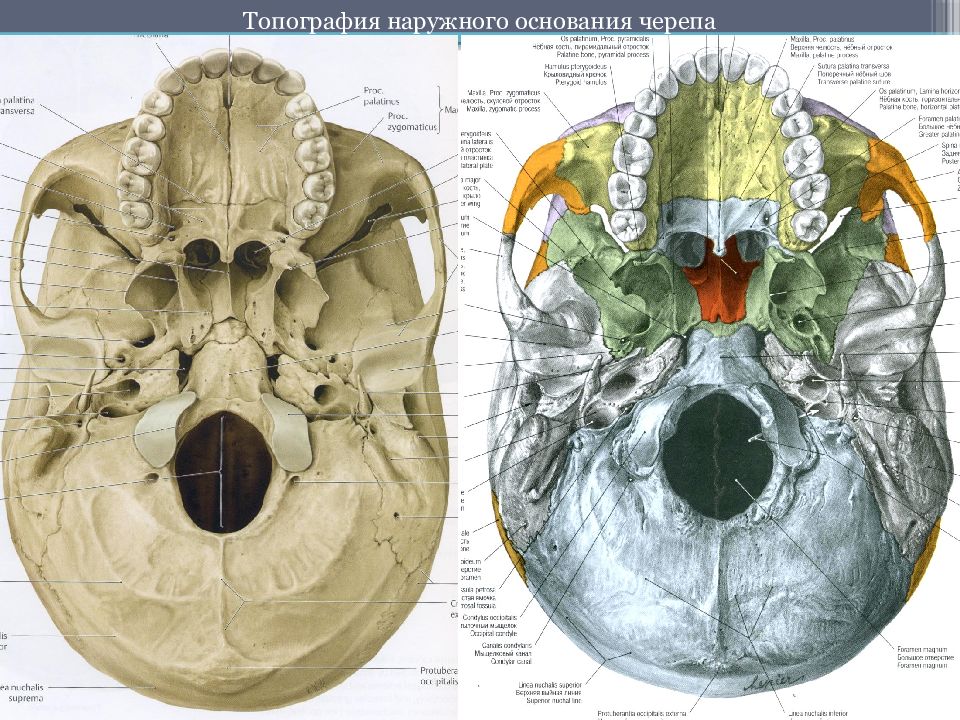

Анатомические детали: Фотографии топографии черепа с нижнего вида